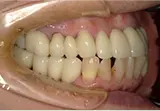

| 年齢/性別 | 60代女性 |

| 主訴 | 前歯が前に出てきた |

| 治療内容 | 全体的に歯周病やむし歯、根の治療(ヘミセクション)を実施。右上の歯にはサイナスリフト術を行い、骨の回復を待った後、半年後に2本のインプラントを埋入しました。 |

| 治療期間 | 9か月 |

| 費用 | 1,298,000円税込 |

| リスク・副作用 | 炎症反応によって術後に腫れや副鼻腔炎が生じることがあります。その程度は、手術の範囲や方法によって異なりますが、多くの場合、時間の経過とともに徐々に治まります。

ごく稀に、下顎奥歯の外科手術後に、唇や顎に痺れを感じることがあります。 |